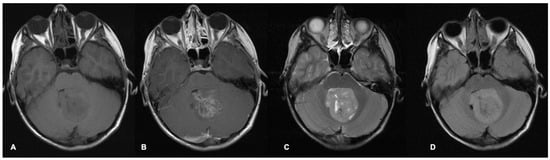

- Nowak, J.; Nemes, K.; Hohm, A.; Vandergrift, L.A.; Hasselblatt, M.; Johann, P.D.; Kool, M.; Frühwald, M.C.; Warmuth-Metz, M. Magnetic resonance imaging surrogates of molecular subgroups in atypical teratoid/rhabdoid tumor. Neuro-Oncology 2018, 20, 1672–1679. [Google Scholar] [CrossRef]